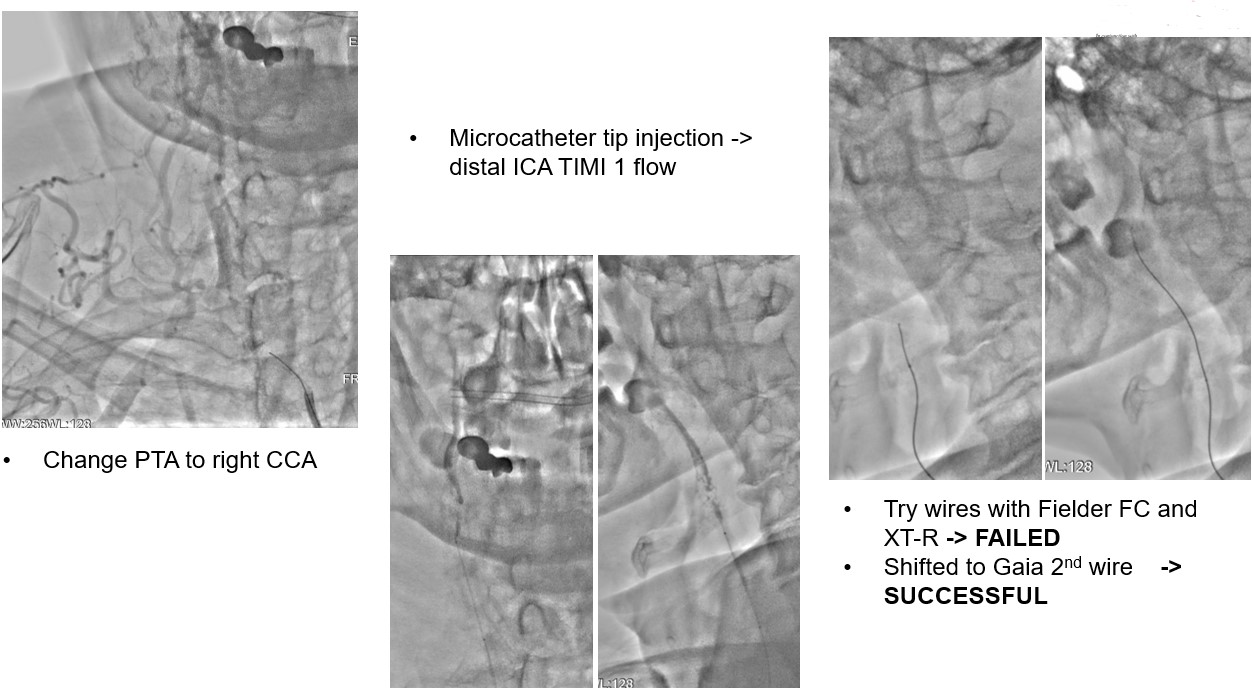

Carotid angiography showed bilateral CCA occlusion with bridge collaterals from vertebral and subclavian artery. Patient refused surgical endarterectomy. Lower limbs angiography revealed right SFA CTO, left SFA distal stenosis.We tried endovascular treatment for left CCA occlusion first but failed.

We tried wiring to left ICA occlusion with microcatheter first but failed.Then we tried PTA for right CCA occlusion. With microcatheter support, Gaia 2nd wire advanced to right ICA difficultly2.0mm small balloon pre-dilateddistal filter placement then carotid stenting smoothly.Patient symptoms improved dramatically and discharged 4 days later.We tried elective PTA for right SFA CTO by bilateral puncture approach. Antegrade from left transfemoral cross over sheath, and retrograde from right POPA.Antegrade failed wiringThen retrograde wire successfully advance to antegrade microcatheter -> Rendezvous -> externalization -> balloon pre-dilate and stenting